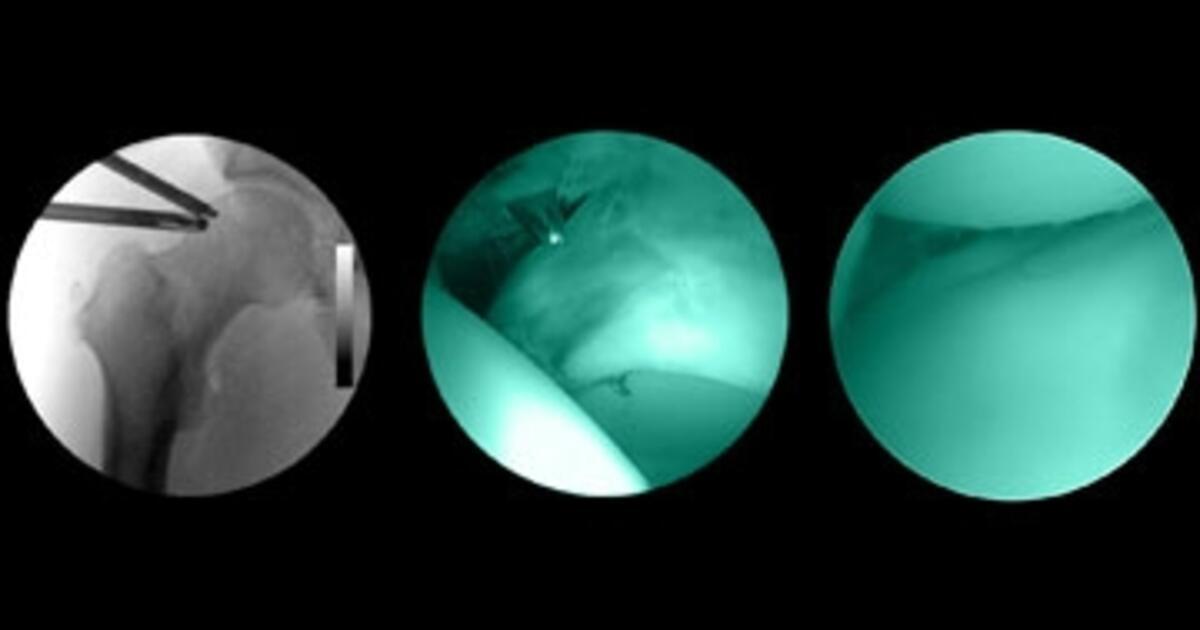

Knee arthroscopy. Surgeon using a keyhole arthroscopy (joint endoscopy Keyhole Surgery Knee Cartilage Video It can be used for inflammation,. Rapid diagnosis is the key to the successful treatment of most painful knee disorders, and we must prevent further damage from occurring. It is usually performed through two very small incisions at the front of the knee which allow a camera to be inserted to give a very clear view of the internal anatomy.. Keyhole Surgery Knee Cartilage Video.

Knee Keyhole Surgery Hospital Arthroscopy Operation Stock Photo Keyhole Surgery Knee Cartilage Video A knee arthroscopy is a type of keyhole surgery that us used to investigate and. Knee arthroscopy is a type of keyhole surgery used to diagnose and treat knee pain or other knee problems. This leaflet is about when and how keyhole surgery can be used to flush out the knee joint and remove damaged tissue (bone or cartilage) in.. Keyhole Surgery Knee Cartilage Video.

Knee keyhole surgery hospital arthroscopy operation medical procedure Keyhole Surgery Knee Cartilage Video This leaflet is about when and how keyhole surgery can be used to flush out the knee joint and remove damaged tissue (bone or cartilage) in. Knee arthroscopy is a type of keyhole surgery used to diagnose and treat knee pain or other knee problems. It is usually performed through two very small incisions at the front of the knee. Keyhole Surgery Knee Cartilage Video.